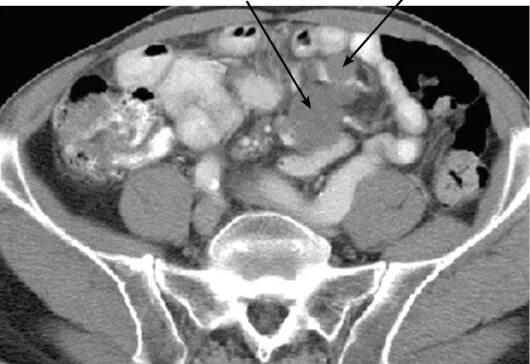

Метастазы при лимфоме